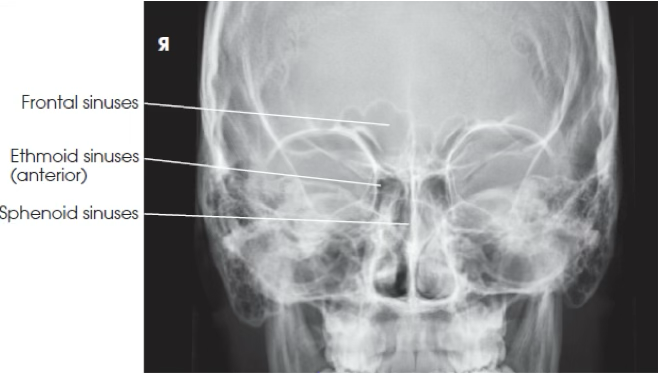

What view is this?

PA skull